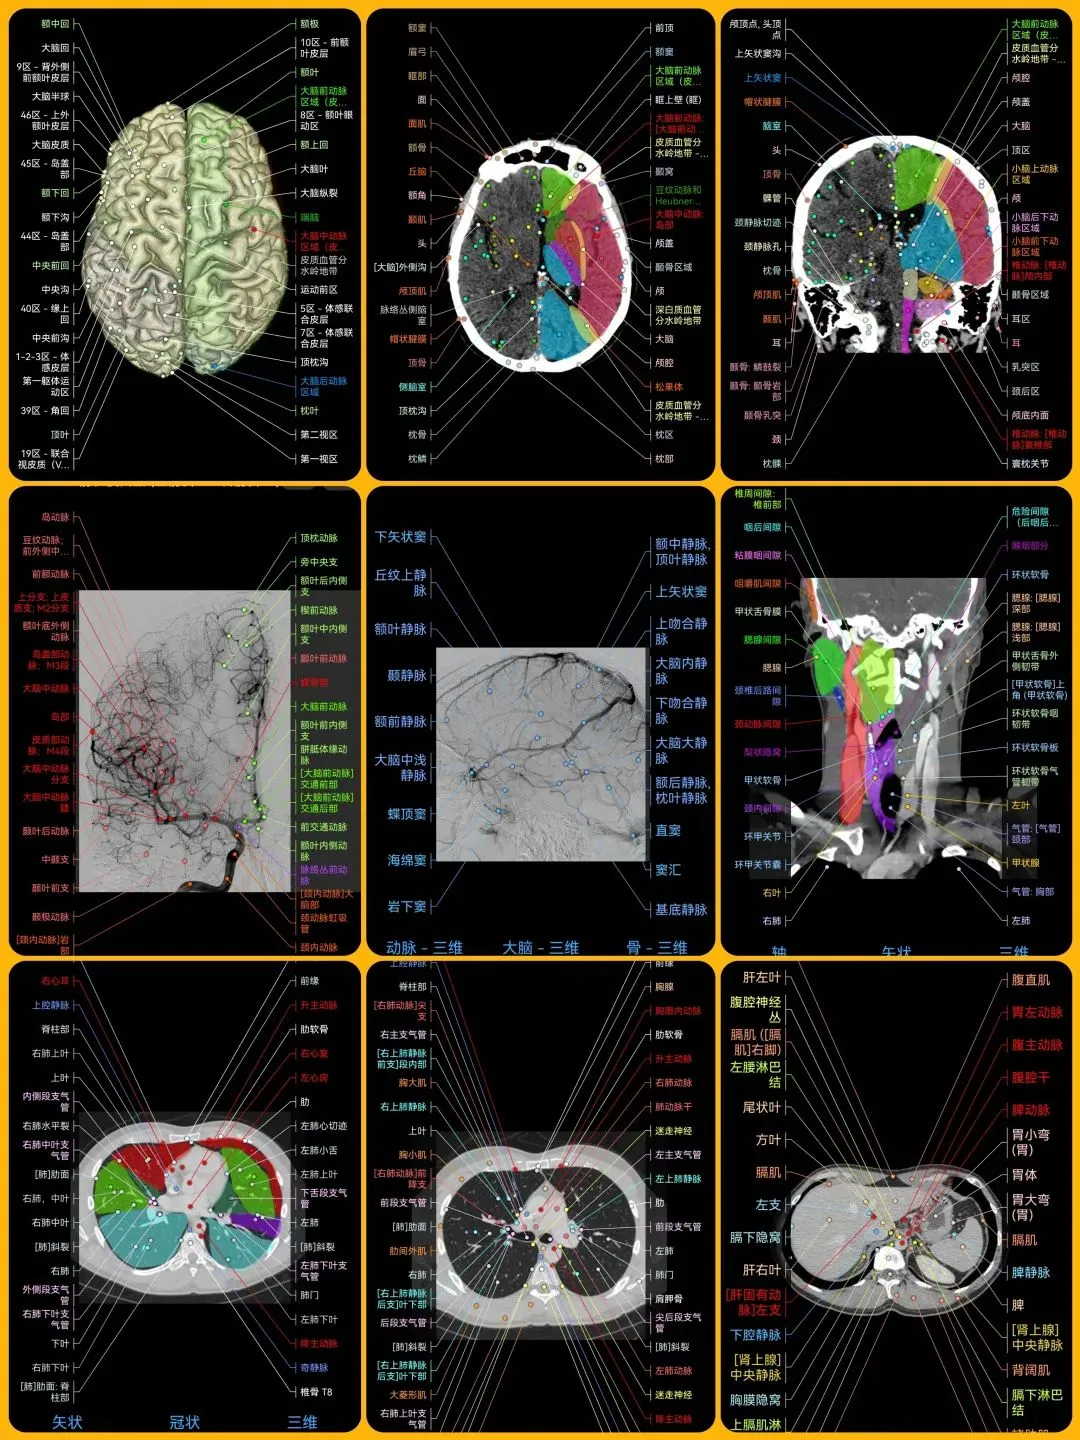

🌈这是国外引进的一款专业影像解剖学习软件。

覆盖了X光、CT、MRI、断层大体解剖、核医学、介入造影、医学插图等多个模块,覆盖全身各个系统的影像解剖(正常解剖结构,无病例),其中的解剖结构高达87万个,结构标注超精细,超高清图像,历时两年研发设计完成✅。